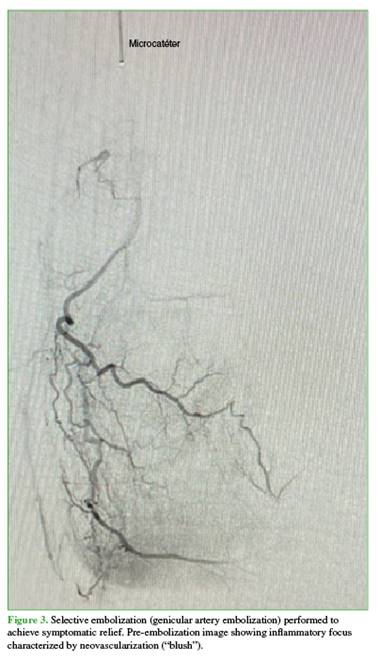

The patient reported marked symptomatic relief following embolization (Figure 3).

The technique consists of superselective embolization of genicular arterial branches supplying areas of synovial neoangiogenesis, seeking a controlled reduction—though not complete occlusion—of flow to the pathological vessels, in order to decrease inflammation and pain while minimizing the risk of ischemia in adjacent tissues (Figure 4).13